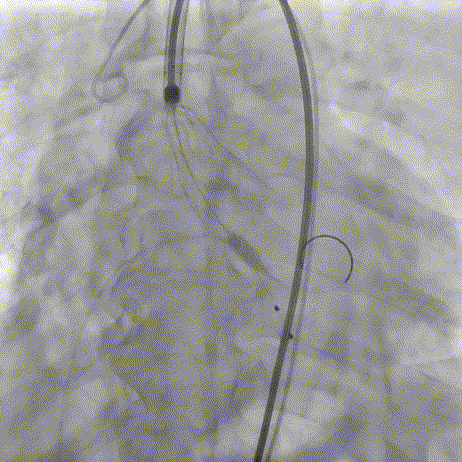

术前主动脉根部造影

20mm球囊预扩

AV26瓣膜定位

AV26瓣膜工作位造影

AV26瓣膜释放

术后主动脉根部造影

本例手术为重度钙化二叶式病变重度主动脉瓣狭窄TAVR手术,团块状钙化挤压存在移位瓣周漏风险,术前手术团队对患者进行了全面细致的评估,确定假体瓣膜锚定区域范围,制定术前释放策略。何柳平主任团队通力配合、精准释放,充分利用TaurusElite可回收功能,在瓣膜释放至2/3时,多角度评估瓣膜植入深度、锚定力以及冠脉灌注情况,确认瓣膜植入深度合适、锚定力稳定,缓慢逐个脱钩,进行瓣膜释放。释放后造影显示瓣膜膨胀良好,行血流动力学评估,跨瓣压差从术前100mmHg降至15mmHg,少量瓣周漏,手术圆满完成。